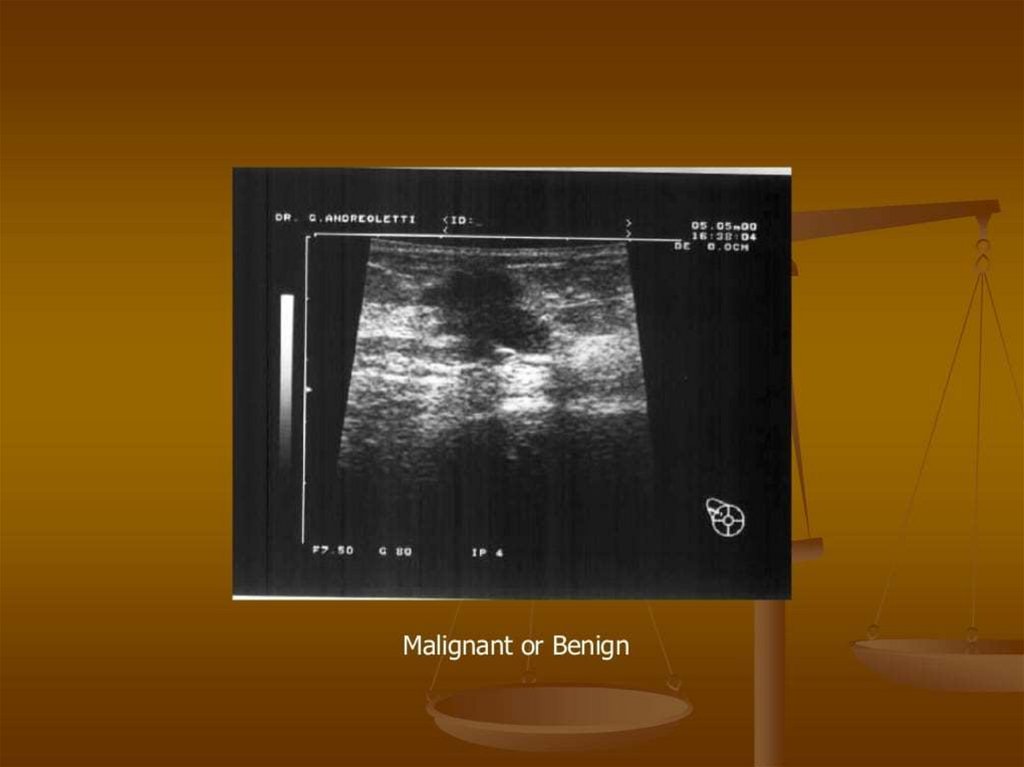

Benign Breast Disease